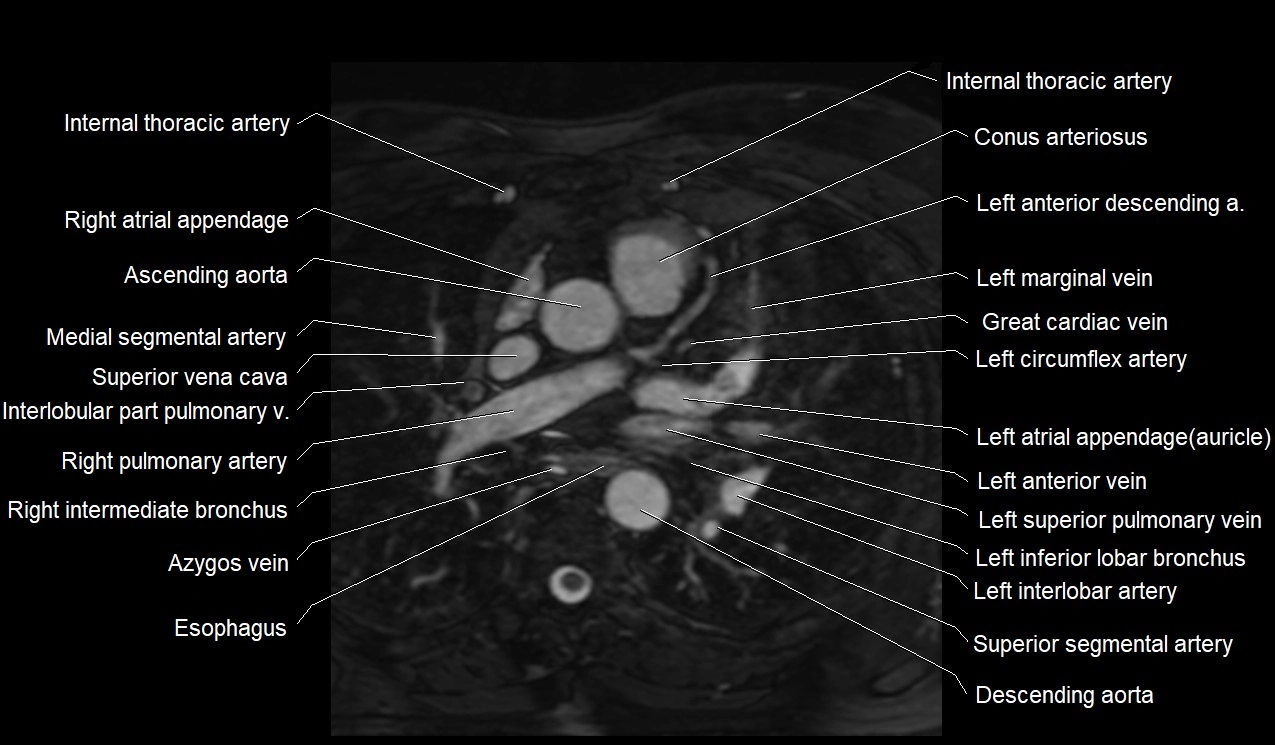

MRI image